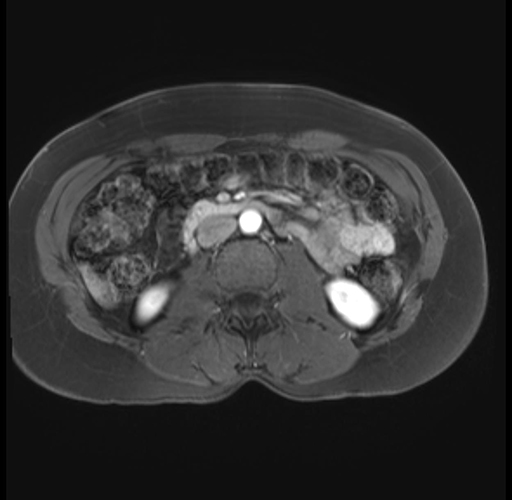

Imaging Analysis

Look through the patient's CT scan to identify any areas of concern for the necessary procedure.

Based on your CT findings, which issue(s) are present and would give reason for "planned slowing down moment(s)" in this case?